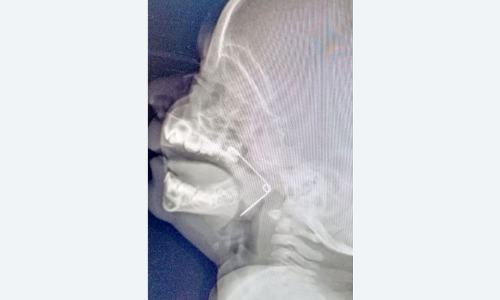

കൊല്ലം: കളിക്കുന്നതിനിടെ പത്തുമാസം പ്രായമുള്ള കുഞ്ഞിെൻറ തൊണ്ടയിൽ കുടുങ്ങിയ സേഫ്റ്റിപിൻ...